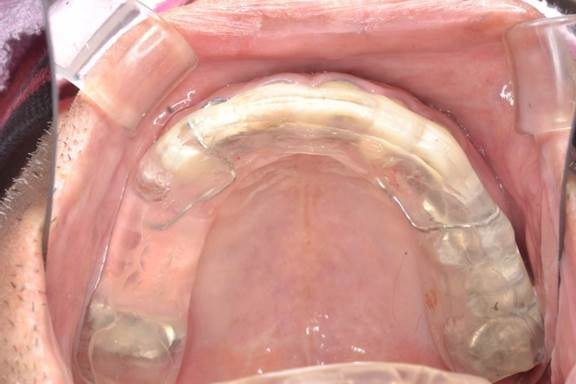

「歯ぎしり・くいしばりで歯が痛い」という相談が増えてきています。上の画像は、「歯ぎしり・くいしばり」が酷く、奥歯が数本ですが歯根破折してしまったため、抜歯を余儀なくされた患者様です。咬んだ時の力をストップさせる奥歯の本数が少なくなるにつれて、前歯に負担が大きくなるため、ハード スプリント(マウスピース)を装着した状態です。

睡眠時の歯ぎしりには、ハードタイプのマウスピースを装着することで上下の歯が接触しないようにして歯を保護する方法があります。不規則な生活習慣や睡眠の質が歯ぎしりなどの悪習癖を悪化させる要因になっていると考えられるときは、生活習慣の改善を指導します。